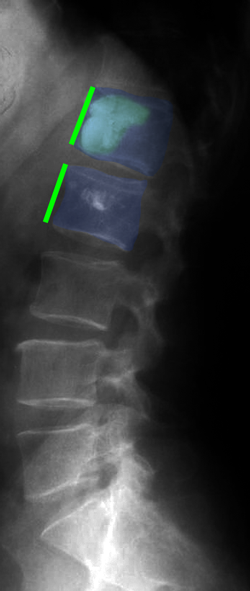

Κάταγμα 01 (φούξια) με μείωση του ύψους του σπονδύλου σε σύγκριση με τον υποκείμενο υγιή σπόνδυλο (μπλέ)(αριστερά). Κυφοπλαστική με ανάταξη του κατάγματος και επαναφορά του ύψους του σπονδύλου στο φυσιολογικό (δεξιά).